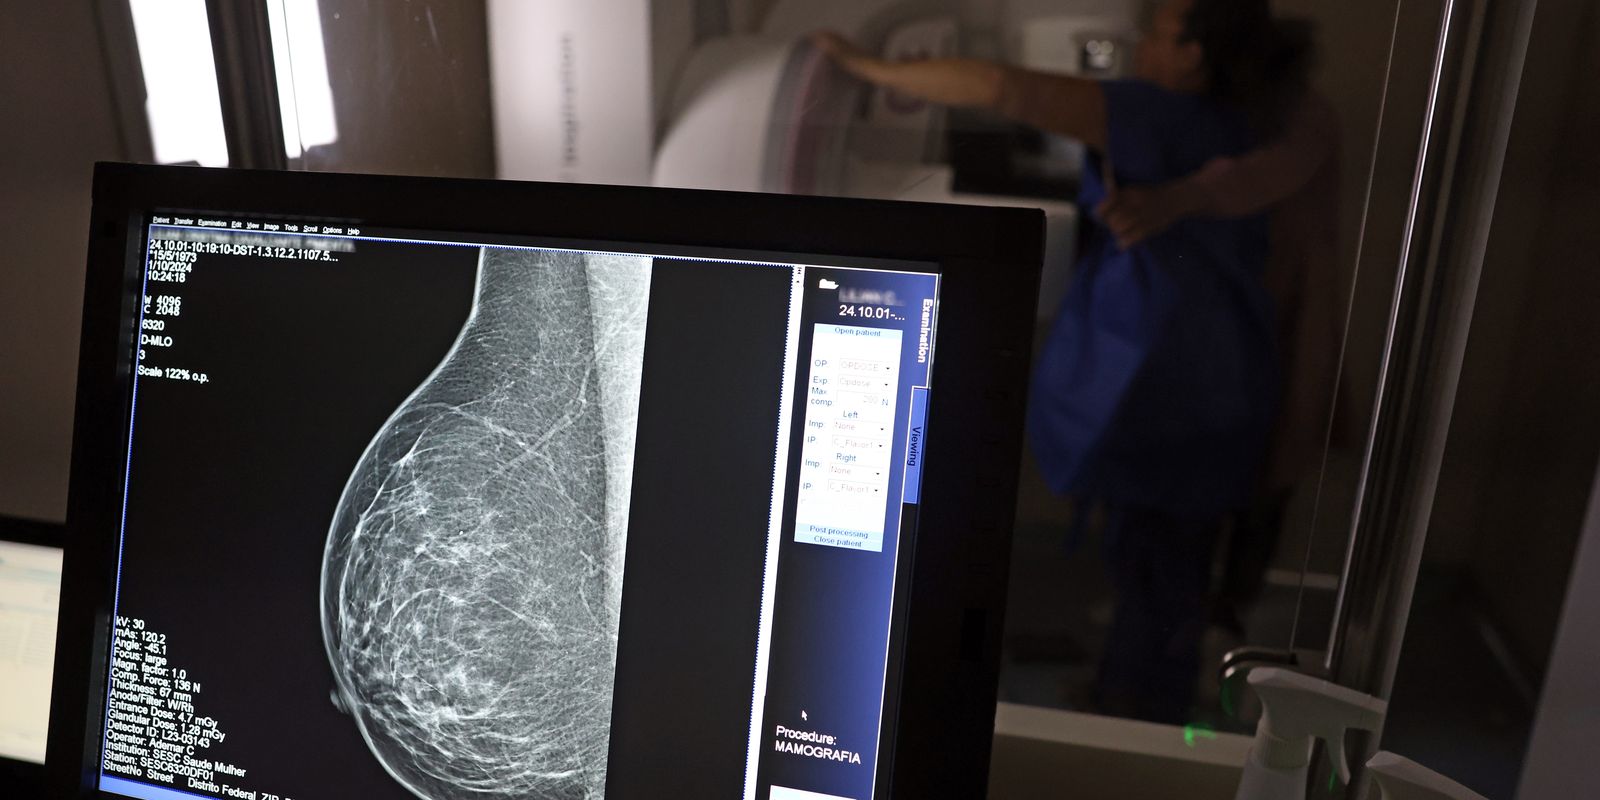

O direito já estava incluído na CLT desde 2018. A partir de agora, as empresas passam a ser obrigadas a divulgar essa informação, além de outras relacionadas a campanhas oficiais de vacinação contra o HPV e sobre o acesso a serviços de diagnósticos de cânceres de mama, próstata e de colo do útero.

O texto estende o uso das folgas também para a realização de exames preventivos do HPV, além dos de câncer que já estavam previstos na legislação anterior. A a Lei 15.377 foi sancionada pelo presidente Luiz Inácio Lula da Silva, e publicada na edição do Diário Oficial da União (DOU). >> Siga o canal da Agência Brasil no WhatsApp